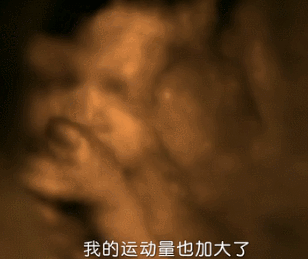

做超声波检查时,

宝宝摆了一个“V”的手势,遮住了脸。

有些孕妈做四维彩超时也会碰到这样的状况,有时宝宝会捂着脸,有时甚至是屁股对着孕妈,就是不给正脸,做个检查要折腾三四遍,不少孕妈只想来自内心的呐喊:娃呀...你就不能配合一点吗?